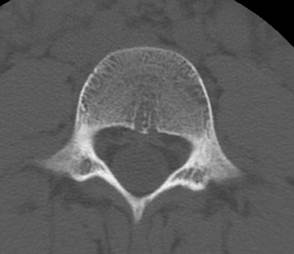

Для

сравнения: четвертый поясничный позвонок, межотростчатая зона, патологии не

выявляется. Костная линия непрерывная,

прослеживается начало нижних суставных отростков, пластинки дуги и оститстого

отростка.